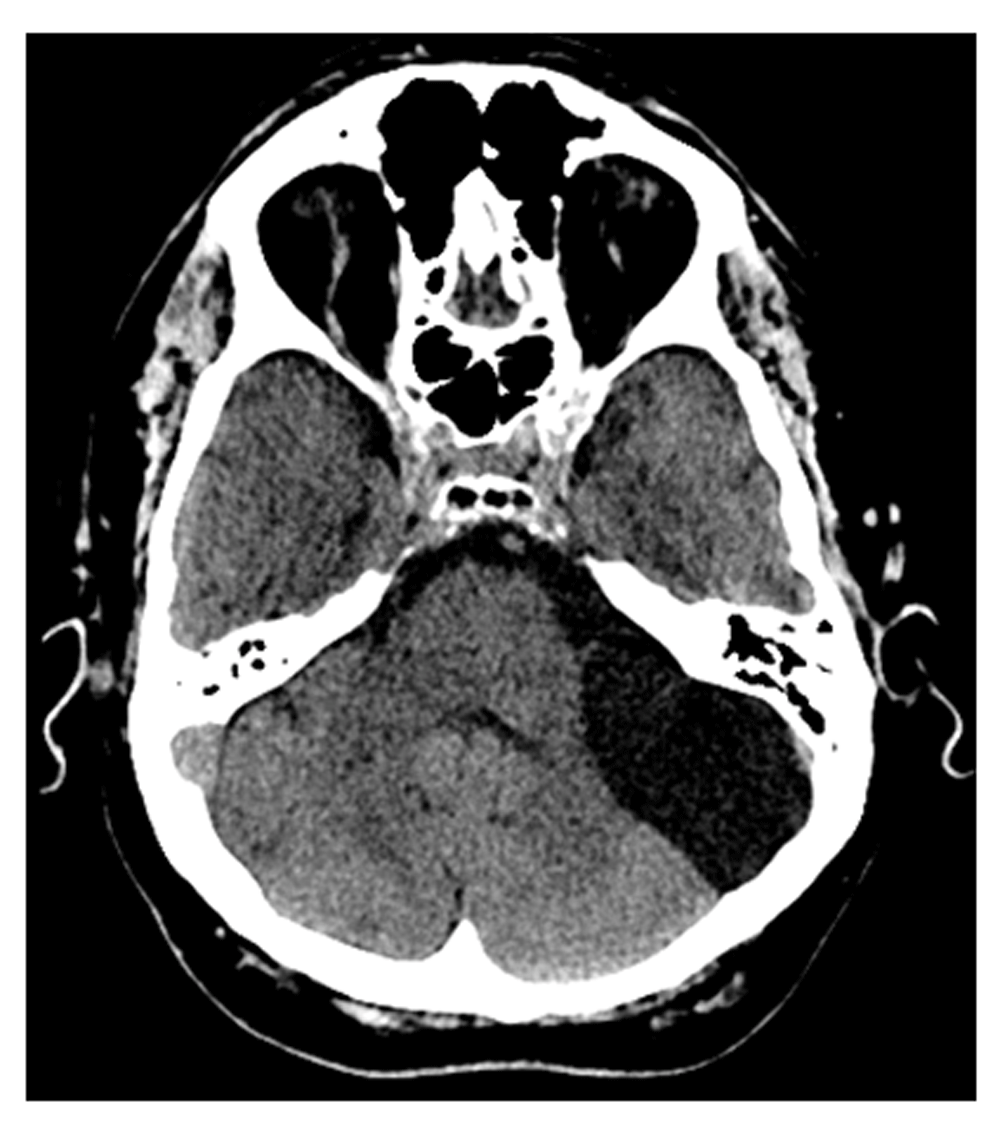

The patient was diagnosed in 1993 with Classic Hodgkin Lymphoma, nodular sclerosis subtype, stage IVB, achieving complete remission after first line chemotherapy. Since then, the patient suffered several relapses and underwent radiotherapy, one autologous bone marrow transplant in 1998, as well as an allogenic stem cell transplant in 2001, followed by several lines of chemotherapy. From October 2018 to the admission at the outpatient clinic, the patient was taking Brentuximab due to a hepatic hilar lesion. Throughout image assessments, a large left infratentorial arachnoid cystic lesion was being monitored. (Figure 1).